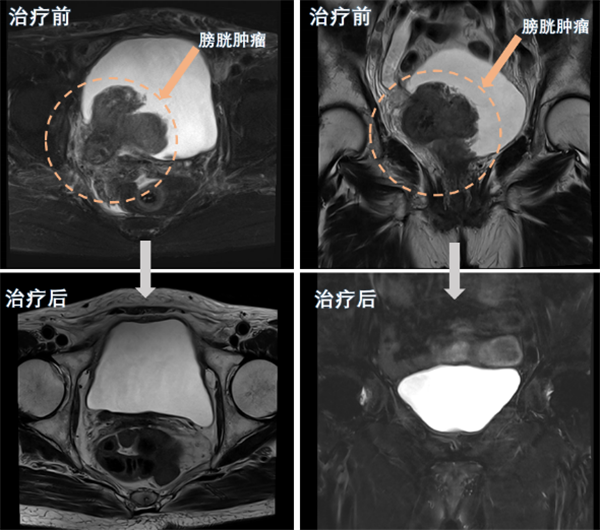

近日,小妲己直播app (简称小妲己直播app )泌尿外科团队为一名80岁高龄的巨大膀胱肿瘤患者实施了经尿道膀胱肿瘤剜除术及术后精准综合治疗,成功保住了该患者的膀胱。经过四个周期的综合治疗后,患者膀胱恢复完好,未见肿瘤复发。该手术的成功,标志着小妲己直播app 泌尿外科在膀胱癌诊治和保膀胱治疗技术方面取得了新突破。半年前,80岁的苏奶奶(化名)因反复无痛性肉眼血尿在当地医院就诊,经...